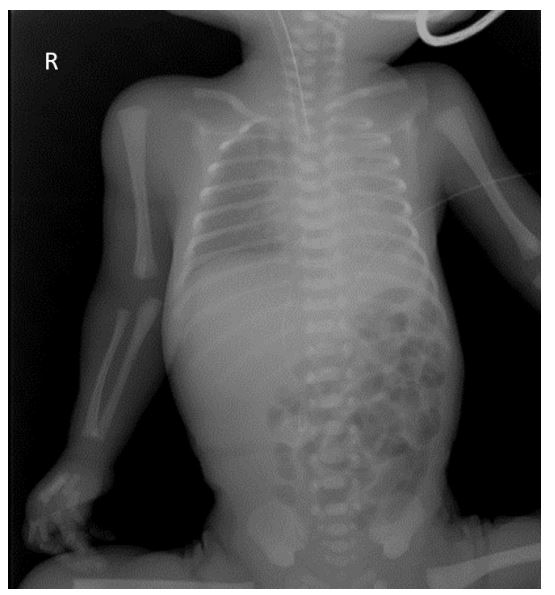

Internal rotation of the right upper arm was noted along with swelling and ecchymosis of the proximal soft tissues. Physical examination of the neck, clavicle, shoulder, and arm revealed no palpable abnormalities. Discomfort was noted with shoulder mobilization. Active range of motion and muscle strength could not be properly assessed. No abnormalities were observed in elbow, wrist, or finger motion. Neonatal brachial plexus palsy was initially considered; however, a shoulder dislocation was suspected after an initial radiograph on the first day of life (Figure 1).

Figure 1 Plain chest radiograph showing no apparent fracture of the right arm. The asymmetry in the joint spaces of the shoulders with lateralization of the right humerus in the shoulder joint falsely suggested a shoulder dislocation.